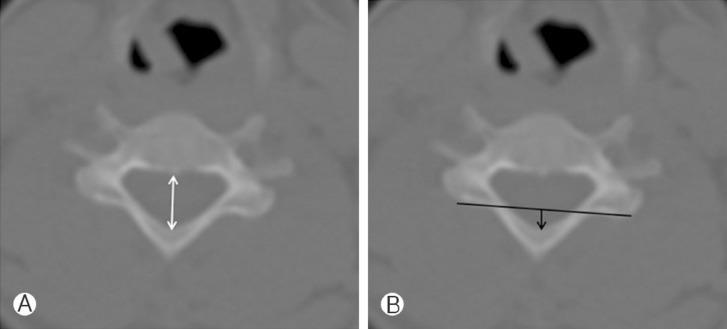

From PET/CT, axial bone-window CT of 83 young adults (20-29 years) were obtained, and we measured AP diameters of C3, C5, C7, T1, T4, T8, T12, L1, L3, L5 and S1. We also measured exposed AP diameter of C3, C5, C7, T1 and T2 above imaginary line for laminectomy.

The shortest mean AP diameter was at C5 (14.5±1.5 mm), and the longest was at S1 (17.4±2.3 mm). AP diameter increased from C3 (14.6±1.1 mm) to T1 (16.1±1.2 mm) at cervical spine. In the thoracic spine, the diameter gradually decreased from T1 (16.1±1.2 mm) to T8 (14.6±1.3 mm) and increased to T12 (16.7±1.2 mm). The diameter decreased from L1 (16.7±1.3 mm) to L3 (15.7±1.9 mm), and it increased to S1 (17.4±2.3 mm) at lumbar spine. Exposed AP diameter above imaginary line for laminectomy was the longest at C3 (4.8±1.2 mm) and gradually decreased to T1 (3.3±0.9 mm) and T2 (0 mm).

Spinal AP diameter was the shortest in the mid-cervical area (C5) and increased to the upper thoracic area. From the upper thoracic vertebra, the diameter gradually decreased to the mid-thoracic vertebra (T8) and then increased to the lower thoracic vertebra. Lumbar vertebra also was similar with thoracic vertebra. Below T2, there was no exposed dural sac after laminectomy. This means that restenosis by post-laminectomy membrane formation can occur above T1.

从PET/CT获取83名20 - 29岁年轻成年人的轴向骨窗CT图像,测量C3、C5、C7、T1、T4、T8、T12、L1、L3、L5和S1的前后径。我们还测量了椎板切除假想线上方C3、C5、C7、T1和T2的暴露前后径。

平均前后径最短处为C5(14.5±1.5mm),最长处为S1(17.4±2.3mm)。颈椎处前后径从C3(14.6±1.1mm)至T1(16.1±1.2mm)增大。胸椎处,直径从T1(16.1±1.2mm)逐渐减小至T8(14.6±1.3mm),然后增大至T12(16.7±1.2mm)。腰椎处直径从L1(16.7±1.